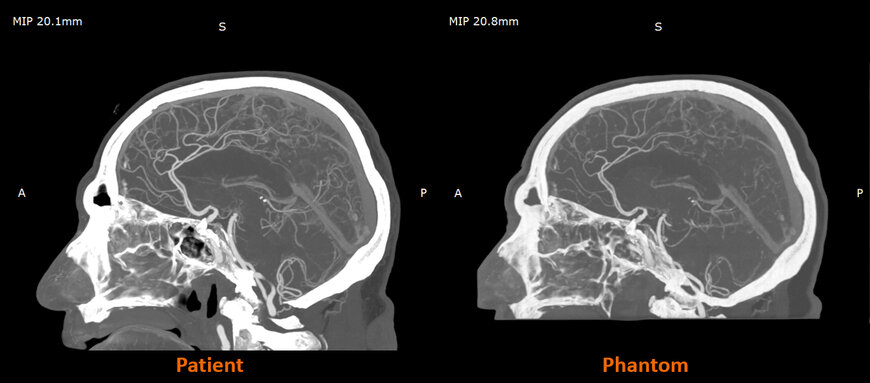

Research carried out with Siemens Healthineers has demonstrated that RadioMatrix-based phantoms can reproduce human tissue radiodensity with deviations as low as single Hounsfield units in key structures, including grey matter and venous anatomy. The partnership also showed that combining Stratasys Digital Anatomy™ technology with the radiopaque material enables models that preserve fine anatomical detail and pathological variations while remaining consistent across prints.

Work in the UK with partners such as CPI and Beaumont Hospital is illustrating how radiographically realistic phantoms can raise the fidelity of imaging-based training. Cerebral angiography models printed with RadioMatrix are used to create controlled, repeatable practice environments—conditions that are difficult to achieve with cadavers or standard phantoms.